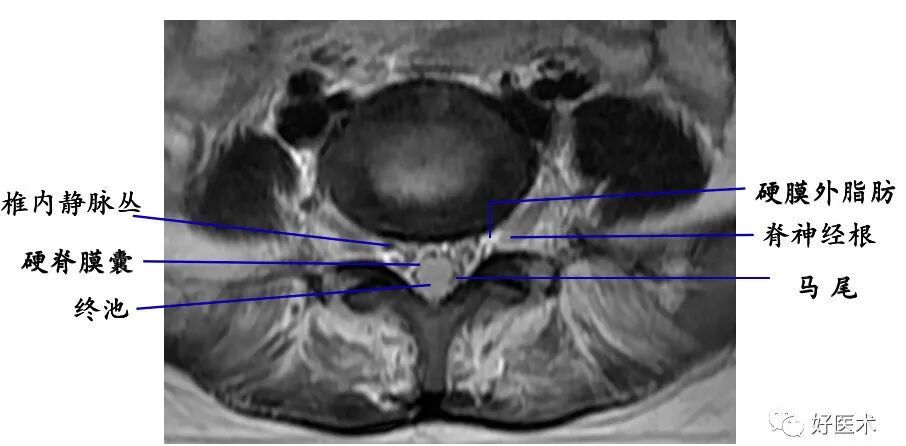

4. 椎管及内容物

硬膜外脂肪:低密度影

硬脊膜囊:呈圆形或椭圆形软组织密度影。CT平扫不能区别硬脊膜囊、脑脊液和脊髓。

椎内静脉丛:位于硬膜外间隙内,在CT平扫上不能单独显示,增强扫描呈点状高密度影。

脊髓:位于椎管中心呈中等信号影

脑脊液:

T1WI上呈低信号;

T2WI上呈高信号影。

脊神经根:中等信号条状或圆点状影。

硬膜外脂肪组织:

T1WI上呈连续条状或带状高信号;

T2WI上呈中高信号。

椎内静脉丛:呈网状略低信号影。